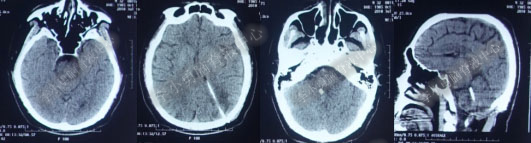

2016年5月9日因“间断性眩晕半月,恶心呕吐一周”以“梗阻性”脑积水,第1次住入北京某企业三级医院神经外科内镜组。2016年5月10日(入院后第2天)行头部MRI(图-1)检查示脑室系统扩张。

图-1:2016年5月10日头部MR